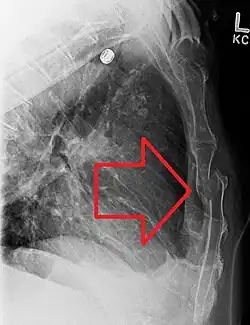

A displaced sternal fracture as seen on plain X-ray

X-rays of the chest are taken in people with chest trauma and symptoms of sternal fractures, and these may be followed by CT scanning.[13] Since X-rays taken from the front may miss the injury, they are taken from the side as well.[14]